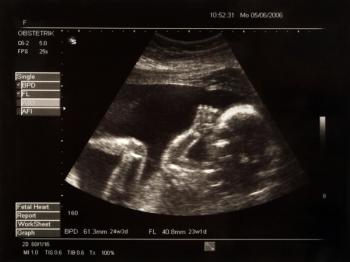

Despite current recommendations to perform a fetal echocardiogram in all in vitro fertilization (IVF) pregnancies, recent study findings show that may not be necessary.

Despite the inadvisability of performing early amniocentesis (EA) before 15 gestational weeks due to a high rate of miscarriage, a retrospective cohort study has found no significant difference in the procedure-related risk of miscarriage between EA, at around 14 weeks gestation, and mid-trimester amniocentesis (MA).